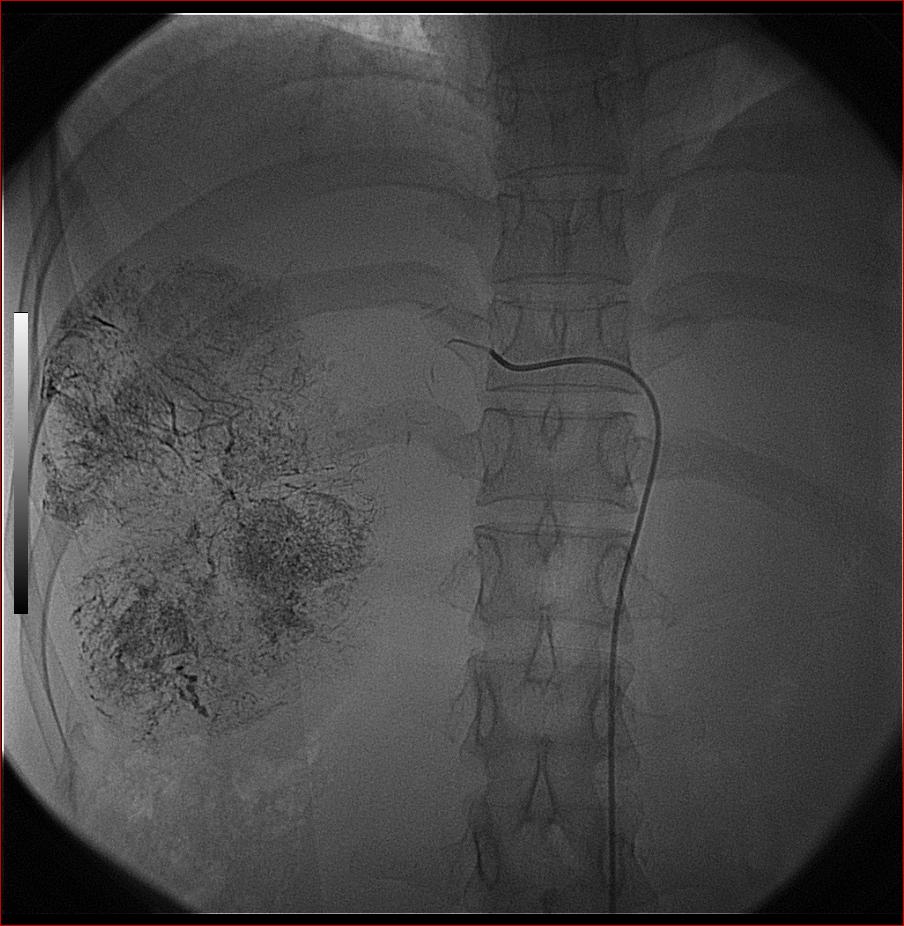

标题: DSA0138:F38Y,肝脏病变

第一次:

好牛的,右肝动脉发自肠系膜上动脉,不用微导管分次进行末梢栓塞,肿瘤染色完整。再次学习了。